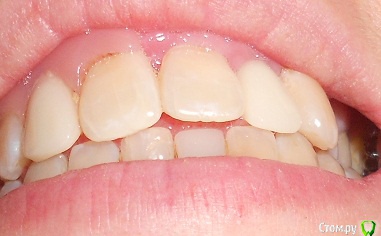

Добрый день, прошу проконсультировать, как поступить в моей ситуации.Прикус как могла сфоткала, сейчас проблема в отсутствии 2х верхних резцов, на их место поставила импланты-но они не прижились-в качестве наиболее вероятной причины выдвигают-недостаточность места, близость к корням соседних зубов.Возможно ли в моем случае ситуацию исправить брекетами.Прикус по-моему неправильный, ВЧ узкая, перекрытие НЧ есть в р-не передних зубов и задних, в середине картина не очень.Возможно ли немного расширить ВЧ. И беспокоит не будут ли смещаться зубы на место отсутствующих?Сейчас на месте одной из двоек съемная бабочка на месте другой имплант который нужно удалять.

Вы правильно обрисовали картину. У вас дефицит места для  "двоек" ,  также перекрестный прикус слева  (справа Вы не показали) (обратное перекрытие зубов, что чревато для сустава.) Также отсутствие верхнего бокового зуба ("пятерка"),  также ретенированные восьмерки (их надо удалять), ну и качество пролеченных зубов оставляет желать лучшего.